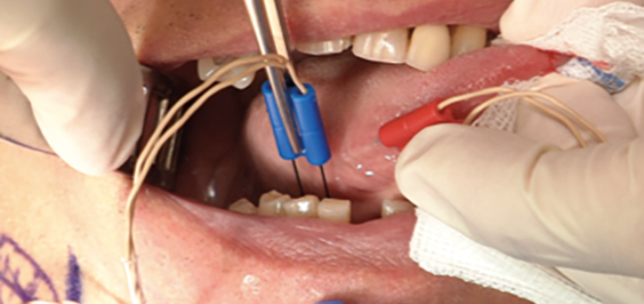

KTP laser in the office